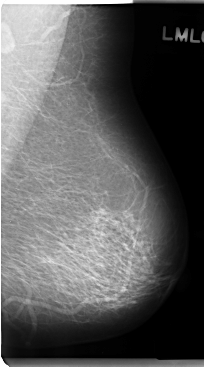

C_0285_1.LEFT_MLO

LEFT_MLO LINES 4760 PIXELS_PER_LINE 2640 BITS_PER_PIXEL 12 RESOLUTION 50 NON_OVERLAY

LESION_TYPE CALCIFICATION TYPE FINE_LINEAR_BRANCHING DISTRIBUTION CLUSTERED

ASSESSMENT 4

SUBTLETY 5

PATHOLOGY BENIGN

SUBTLETY 4